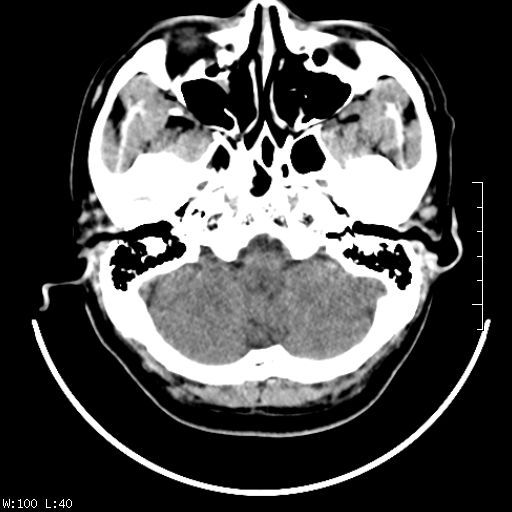

标题: CT22236:男,45,经常头痛。看看脑干正常吗? [打印本页]

标题: CT22236:男,45,经常头痛。看看脑干正常吗?

未见明显异常,建议ct增强或mri检查。

没见异常密度及形态改变啊,我认为是正常的。

颅脑ct轴位平扫颅内未见明确异常。

颅脑ct平扫未见明确异常,必要时mri检查。

颅脑ct平扫未见异常